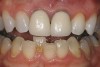

Figure 2  A radiograph finds no pulp chamber in the slightly dark central incisor and a silver point on the darkest lateral incisor. A titrated approach to bleaching was needed using individual tooth treatments.

Figure 2